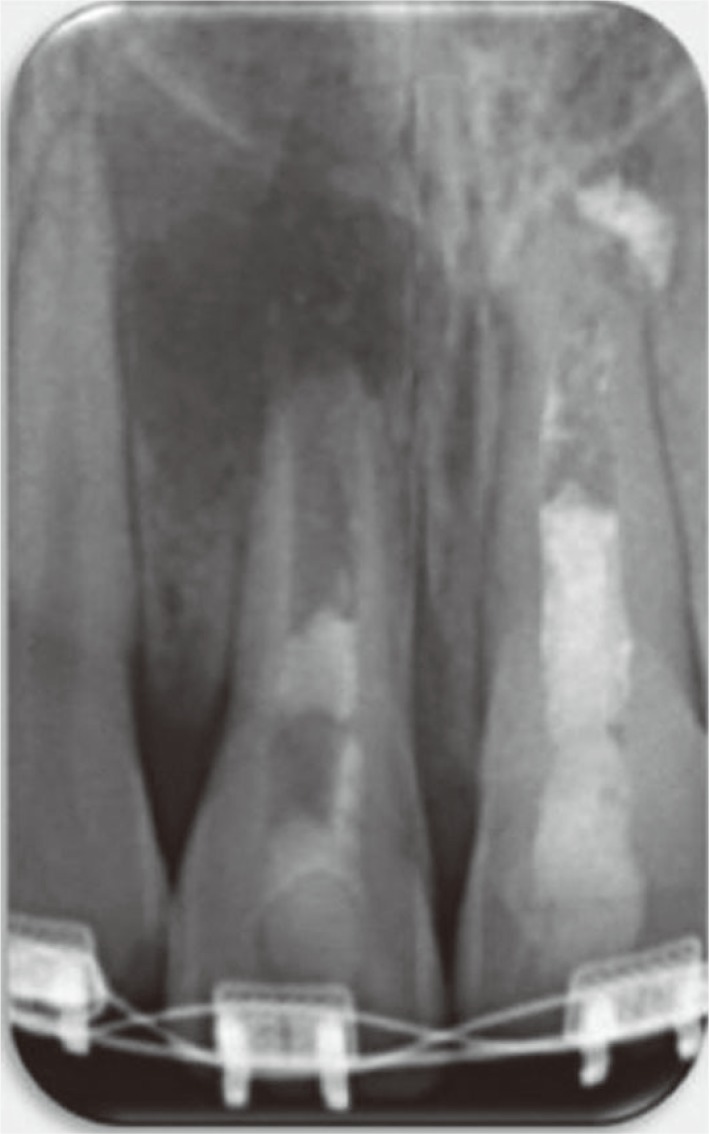

The treatment options were discussed with the patient's mother. It was decided that the patient would benefit from another revascularization procedure rather than regular apexification or an apical plug. A consent form was signed after approval of the proposed protocol to initiate revascularization treatment. A rubber dam was applied, and the tooth was accessed following local anesthesia (1.8 mL of 2% lidocaine with 1:100,000 epinephrine) administration using a dental operating microscope (Global Surgical Corp., St. Louis, MO, USA). The MTA root canal filling was removed with CPR ultrasonic tips (Obtura Spartan Endodontics, Algonquin, IL, USA) set at low power. The vibration of the CPR ultrasonic tips caused the MTA filling materials to break up into pieces, and then the canal was flushed with saline to remove root canal filling debris, irrigated with 20 mL of 5.25% sodium hypochlorite (Henry Schein, Melville, NY, USA), and then rinsed with sterile saline solution. The pulp chamber was carefully dried with paper points and filled with double antibiotic paste (DAP) consisting of a mixture of ciprofloxacin (Ciprobay, Bayer Pharma, Leverkusen, Germany) and metronidazole (Flagyl, Sanofi Aventis, Frankfurt, Germany) in a 1:1 ratio prepared with saline (wt/vol 2.5:1) using a lentulo spiral (Dentsply, Maillefer, Ballaigues, Switzerland). Access was sealed with temporary filling material (Cavit, 3M ESPE, St. Paul, MN, USA), and a radiograph was taken (Figure 2).

Figure 2

Periapical radiograph after placement of double antibiotic paste (DAP).

Figure 2 Periapical radiograph after placement of double antibiotic paste (DAP).